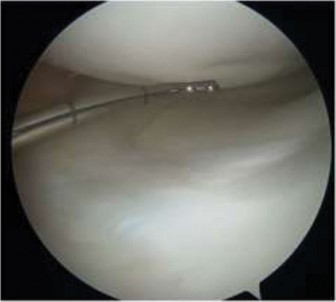

The correct answer is (D). The patient has an unstable lesion on MRI which is acute; therefore every attempt should be made to salvage the lesion. The ideal treatment would be fixation of the lesion although the determination for treatment cannot be made until it is examined arthroscopically. If the lesion is not deemed stable during arthroscopy, then drilling would be a reasonable option (and can be combined with fixation). If the fragment is nonviable, microfracture would be a reasonable option to stimulate fibrocartilage formation as long as the donor site is not too large. Fragment removal and chondroplasty is not ideal for a young patient; particularly one who is engaged in sporting activities. Every attempt should be made to salvage the lesion and/or stimulate new cartilage formation if the fragment is unsalvageable. The lesion is shown arthroscopically (Fig. 10–26). The appropriate treatment option is:

The correct answer is (A). The patient has an unstable lesion on MRI and is demonstrating instability on arthroscopic examination. The fragment is viable therefore fixation of the lesion is optimal. Drilling would be appropriate for a stable lesion but both imaging and clinical findings suggest instability. As the lesion is viable, it should not be removed. Therefore, microfracture and mosaicplasty in the absence of exposed subchondral bone should not be utilized. Objectives: Did you learn...? The clinical presentation and physical examination findings of OCD lesions of the knee?